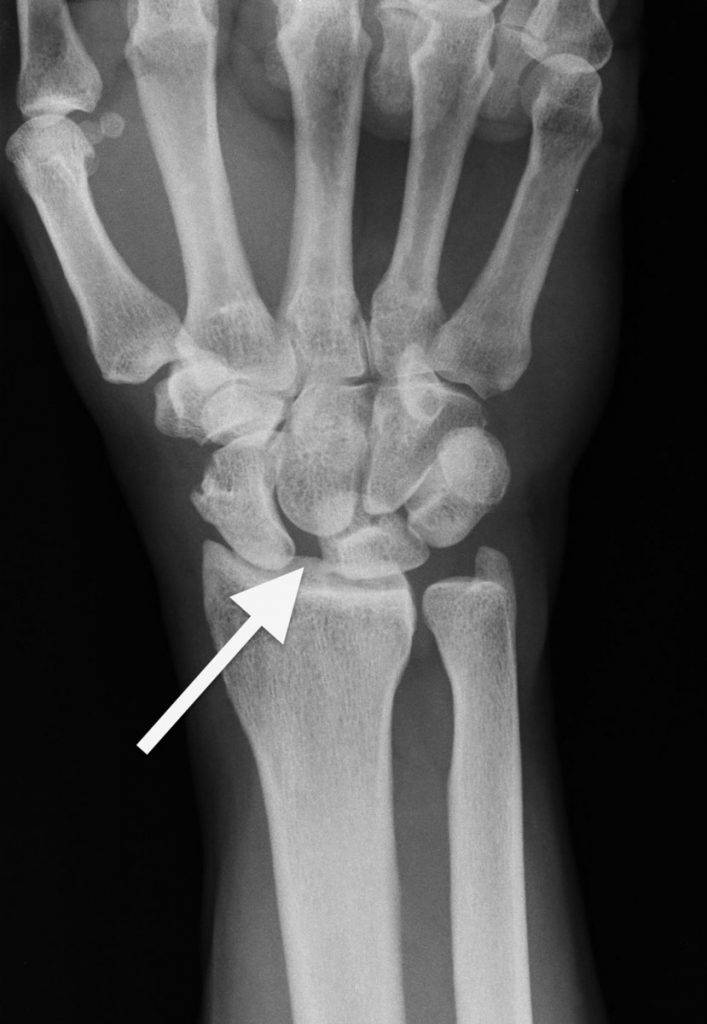

El ligamento que se lesiona más comúnmente en la muñeca es el escafo-semilunar o escafo-lunar (Figura 2), (Ver apartado Lesión del Ligamento Escafo-Lunar). Es el ligamento que se encuentra entre dos de los huesos pequeños de la muñeca: el hueso escafoides y el hueso semilunar. Hay otros muchos ligamentos en la muñeca, pero se dañan con menor frecuencia.

Lo primero que hará el médico será examinarle la muñeca para comprobar si le duele y valorar cómo se mueve. Le tomarán radiografías para verificar que no haya huesos rotos ni articulaciones luxadas. En ciertos casos pueden realizarse otros estudios, como una resonancia magnética (RMN).